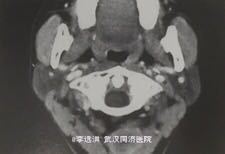

患者,女,34岁,因间歇性头晕,头昏半年入院;患者半年来出现不明原因的间歇性头痛,晕倒;检查血糖正常,体位性低血压明显,为确诊来我院治疗。

查体示颈部触及微小结节,气管位置居中;CT示:颈部迷走神经分支处出现高密度散发结节影,分布在颈部神经包膜边缘,未侵及神经层。

诊断为颈部神经鞘瘤,遂给予手术剥除神经鞘瘤,修复神经。